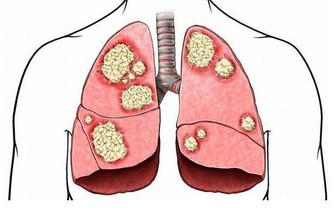

惡性黑色素瘤是皮膚癌的一種,雖然在中國還不是很常見,但是在歐美地區卻是常見的惡性腫瘤之一。在我國不常見並不意味著黑痣對人體是無害的,近幾年來皮膚癌在我國的發病率也逐漸升高,所以我們還是需要了解其產生的原因,事先做好防護措施,防患於未然。

黑痣本身就是我們身體與生俱來的良性腫瘤。後天由於生活環境的影響以及自身各個器官的病變,導致了其進一步惡化為黑色素瘤。